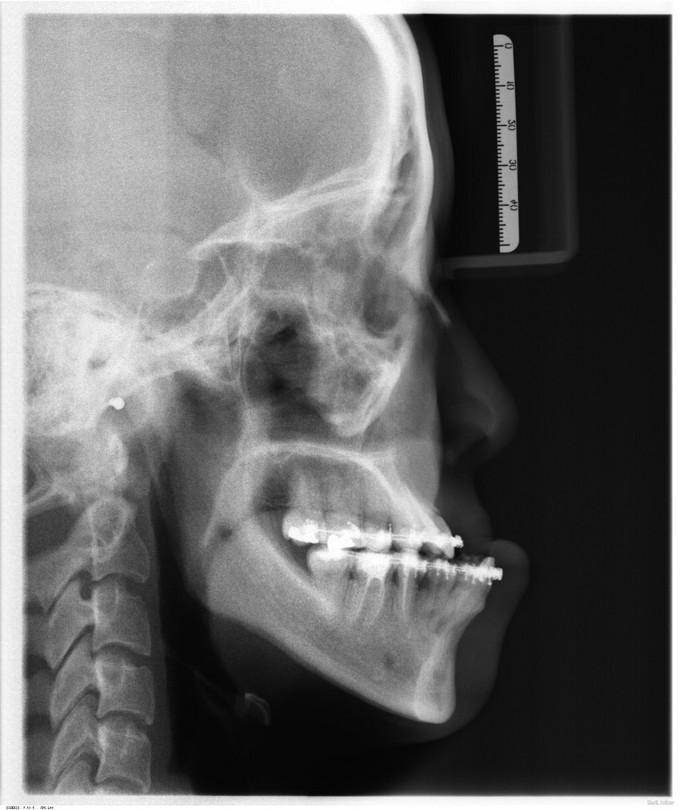

发现下颌前突、上颌后缩数年,于13年行正畸治疗。今为进一步治疗来我院就诊,门诊以"下颌前突、上颌后缩"收入院。

面部发育一般,中线左右对称,上中下比例不协调,上颌后缩,下颌前突,颏顶点正中。左侧颞下颌关节无弹响无疼痛动度正常,右侧颞下颌关节无弹响无疼痛动度正常。张口度4.0cm,开口型正常。上下牙弓关系协调,前牙反合约0.6cm,龋齿无,牙周病无。

入院诊断:1.下颌前突2.上颌后缩3.偏颌畸形,出院诊断: 1.下颌前突2.上颌后缩3.偏颌畸形4.双侧上颌窦粘液囊肿,全麻下行“上颌LefortI型颌骨前徙术+骨内坚固内固定术+双侧下颌升支矢状劈开后退术+双侧下颌骨去骨皮质术+骨内坚固内固定术+双侧邻近瓣转移修复术+双侧上颌窦粘液囊肿摘除术”